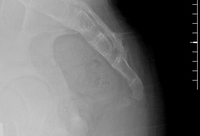

Radiografia sacrococcígea lateral dinâmica de um paciente com coccigodinia crônica idiopática, mostrando 30° de flexão anterior na posição ortostática

Do acervo pessoal do Dr. R. Schrot